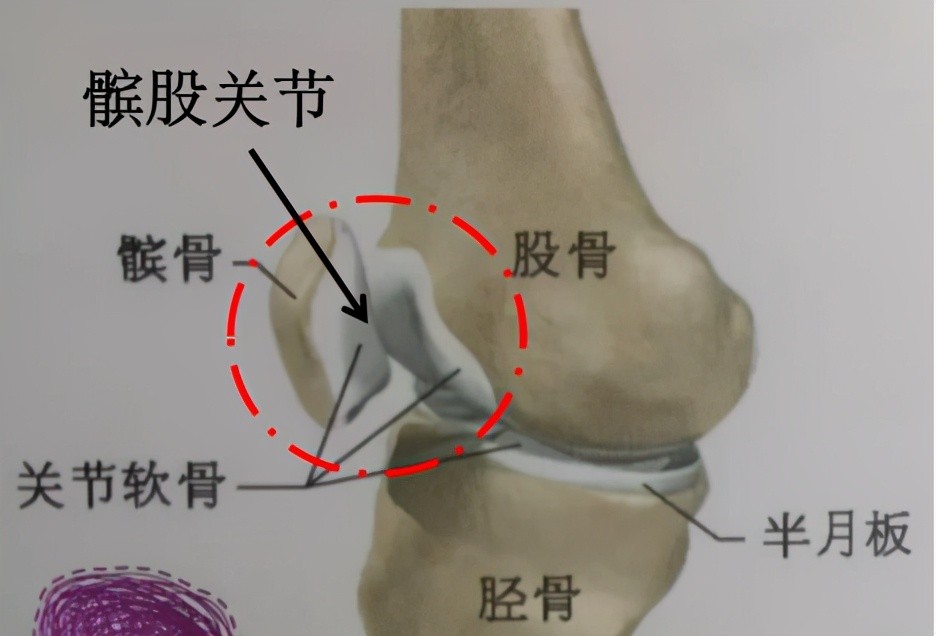

髌股关节炎

这个位置的疼痛在骨科门诊众多膝关节疼痛的患者当中占比相当大,尤其是40-60岁年龄段的人群,膝关节前方的疼痛,大部分都是髌股关节炎导致的。

正常的髌股关节

饱经沧桑的髌股关节

髌股关节炎有哪些表现?

①膝关节前方髌骨的深处疼痛,经常是双侧膝盖都痛。

②走平路疼痛不明显,上下楼梯、蹲和跪时明显。

③久坐之后,站起身那一刻,感觉膝盖酸痛明显。

④走楼梯时膝盖打软腿,没力气。

哪些原因易导致髌股关节软骨磨损?

①经常蹲、跪、上下楼梯,经常爬山。

②运动过度的人群,如长时间跑步、高强度负重深蹲等。

③还有一类人群髌骨的位置先天发育的有些外偏,容易导致膝关节活动时髌股关节紊乱,软骨摩擦受力不均,导致某个位置磨损过大出现疼痛。